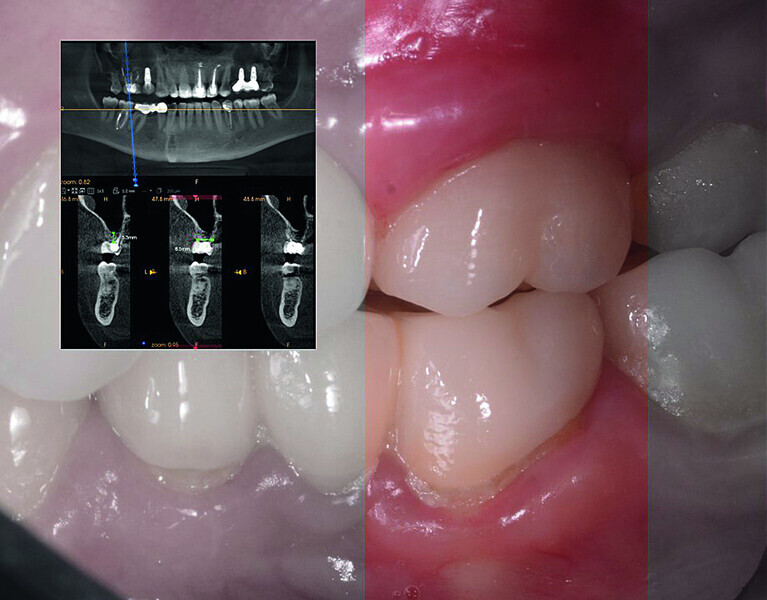

Digital workflow and application of PRF and ozone therapy in oral rehabilitation